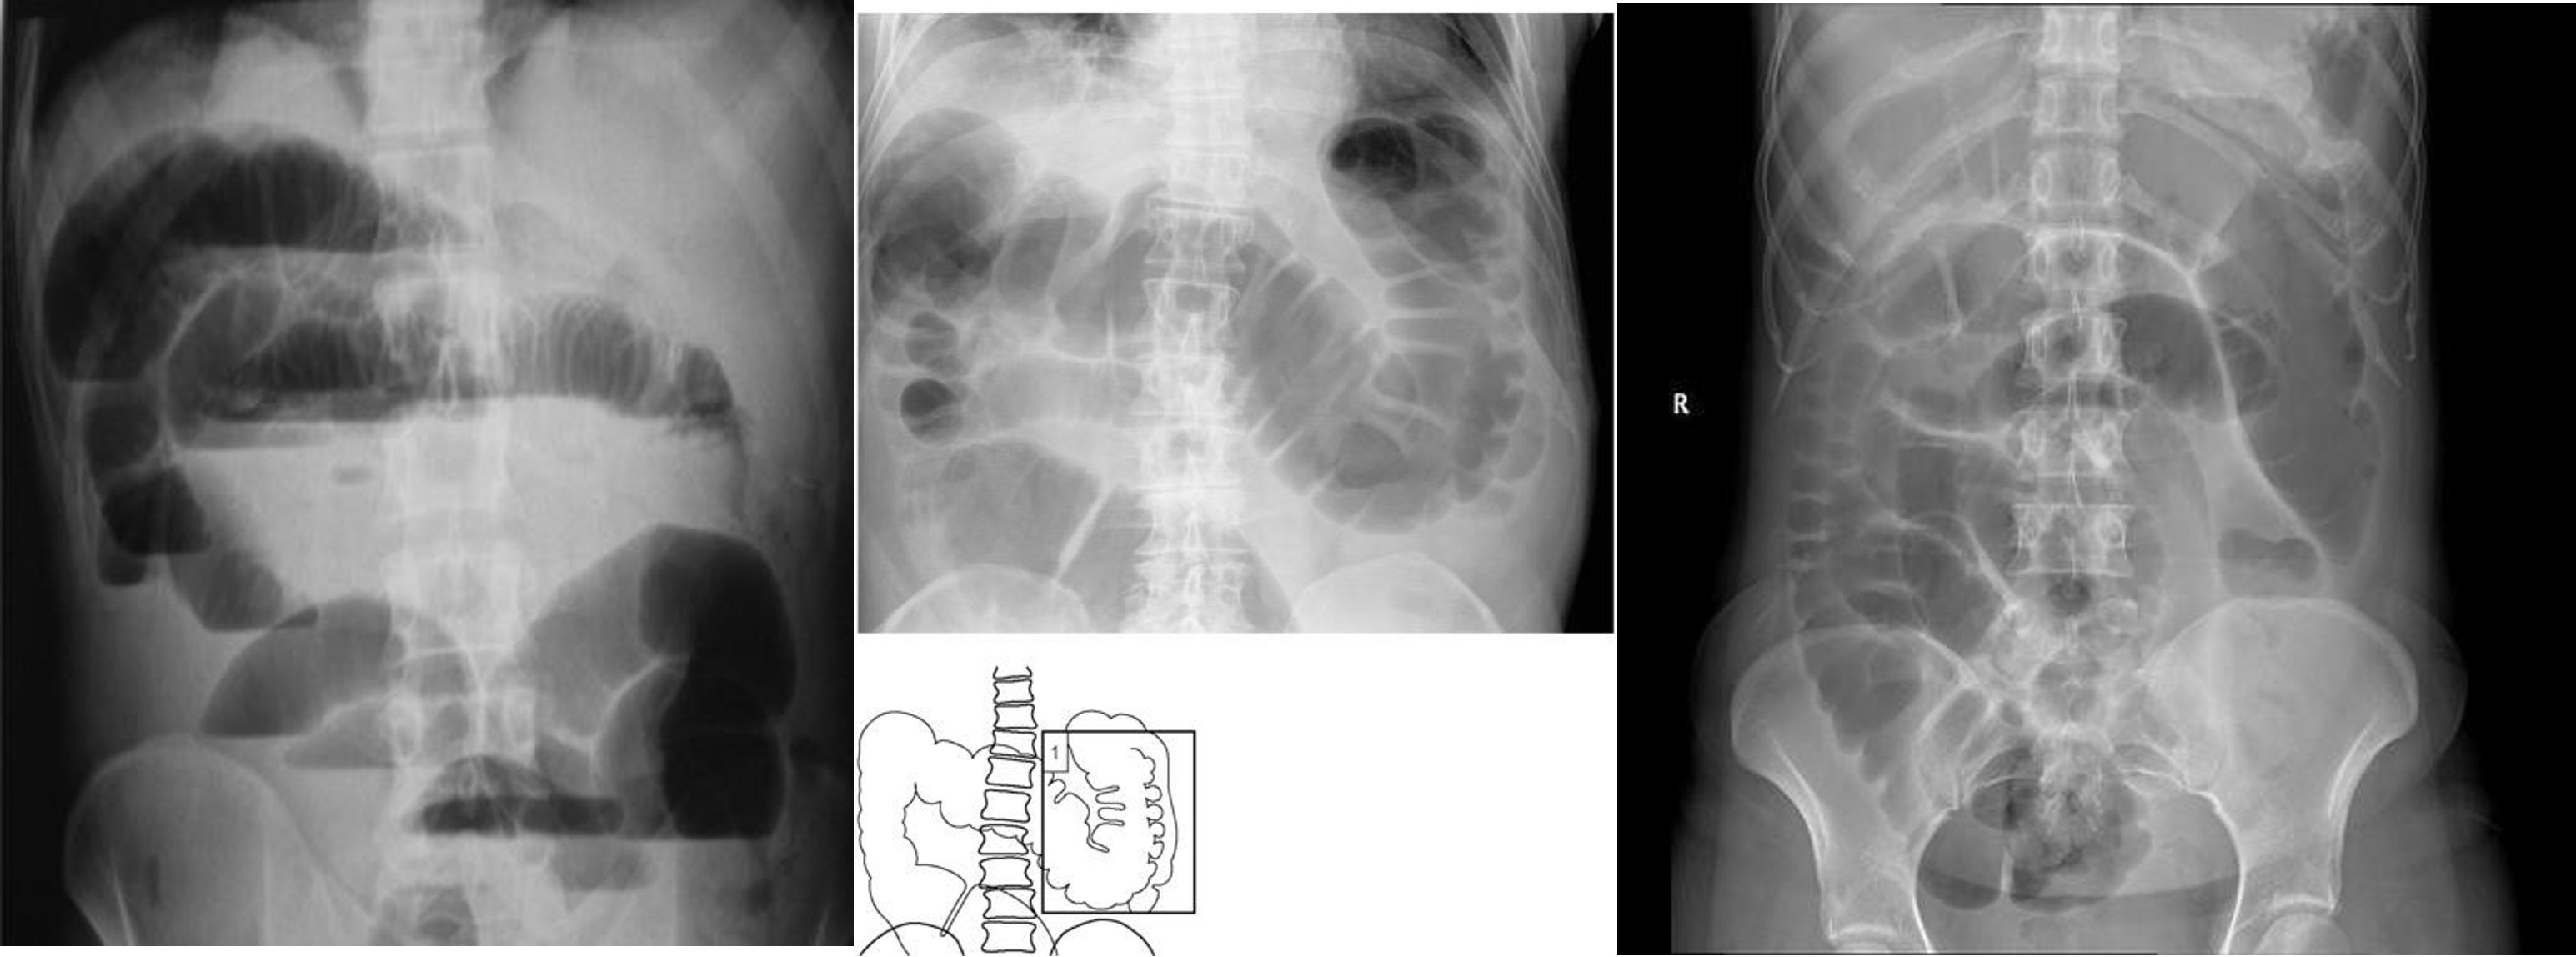

Abdomen Imaging

normal abdominal x-ray - normal gas pattern - lower pole kidney - gastric bubble is found - comment on bone

Free air under diaphragm - most commonly due duodenal perforation - (diff; perforated viscus, peptic ulcer, duodenal, penetrating truama, post surgical 8 days likely to disappear)

- free air

- erect - air fluid levels - should be not more than three - >5 significant 11 found -

- no free air under diaphgram - 8 fluid level, (evidence of bowel obstruction) (adhesion, hernia, IBD; Crohn, cancer, inturcucception, gallstones)

9 air fluids in large bowel - mucosal folds are not completed - highly suggestive of bowel obstruction

- dilated large bowel - mucosal folds are not complete - (diff; cancer, divertuclitis, volvolus, toxic megacolon?)

- if both small and large most likely nonmechanical paralytical illeus